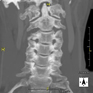

- TC Columna cervical

Prova radiològica que consisteix en obtenir imatges de les vèrtebres cervicals d'alta definició anatòmica, mitjançant l'ús d'un equip de TC (Tomografia Computeritzada). Indicacions: dolor cervical amb/sense irradiació als braços, traumatisme, malformacions congènites. - TC Columna dorsal